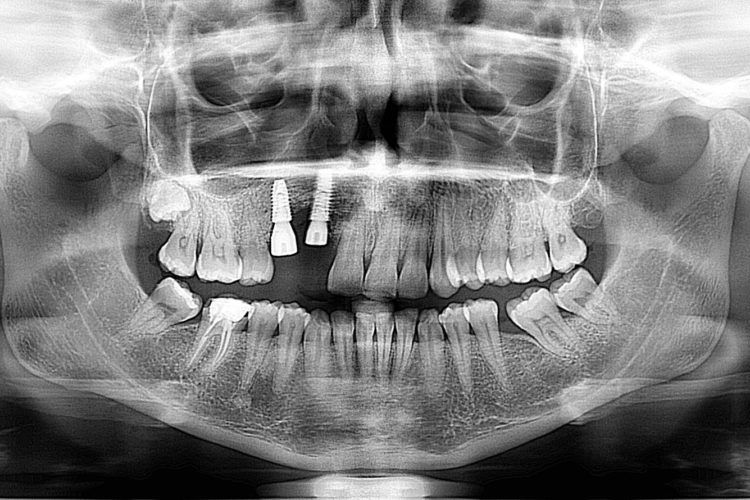

Pacienta in varsta de 39 de ani, a venit in clinica cu pierdere osoasa majora la maxilar in urma unei extractii de canin inclus si pierderea dintelui invecinat. Dupa o interventie de aditie osoasa, pacienta a primit  2 implante DENTIUM pe care s-a efectuat o protezare fizionomica fixa (baza titan plus suprastructura insurubata de zirconiu), cu refacerea conturului gingival si restaurarea functionala a arcadei. Pacientei i s-a propus si redresarea ortodontica pe care a amanat-o pentru o data ulterioara.